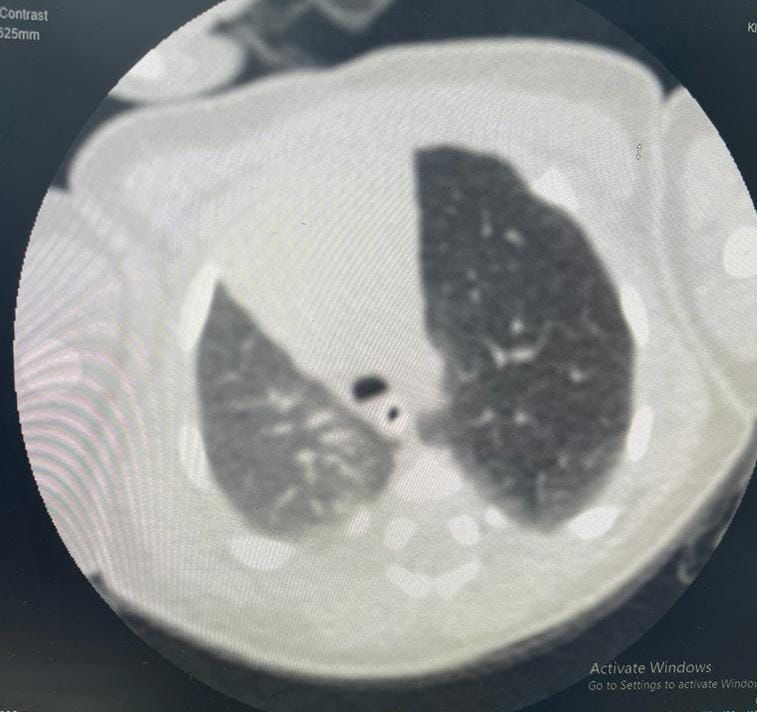

إستقبل مجمع الملك فيصل الطبي بالطائف حالة طفل خديج حديث الولادة يعاني من صعوبة في التنفس، وتم بشكلٍ عاجل عمل فحوصات وتحاليل وأشعة دقيقة للطفل أثبتت وجود تمدد بالفص الأيسر العلوي من الرئة،

وتم تشكيل فريق طبي من عدة تخصصات شملت أطباء جراحة الصدر، وأطباء الرعاية الفائقة للأطفال الخُدج بالمجمع، وبعد دراسة الحالة تم اتخاذ قرار بإجراء جراحة عاجلة ودقيقة لاستئصال الفص الأيسر العلوي من الرئة عن طريق شق صدري محدود بمشاركة الدكتور نادر البرعي استشاري جراحة الصدر، والدكتور جاسر علي استشاري جراحة الصدر، والدكتورة عبير أحمد عبد السلام حسن طبيبة حديثي الولادة.